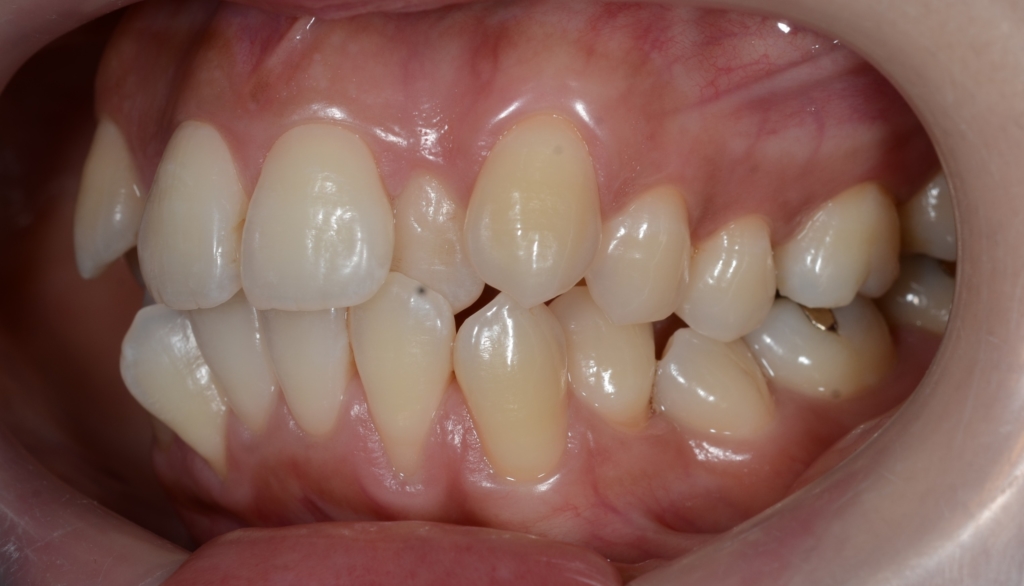

【Before】

#1.顎と歯の不調和による叢生(重度)

#2.上顎前突(奥歯の噛み合わせ)

と診断しました。